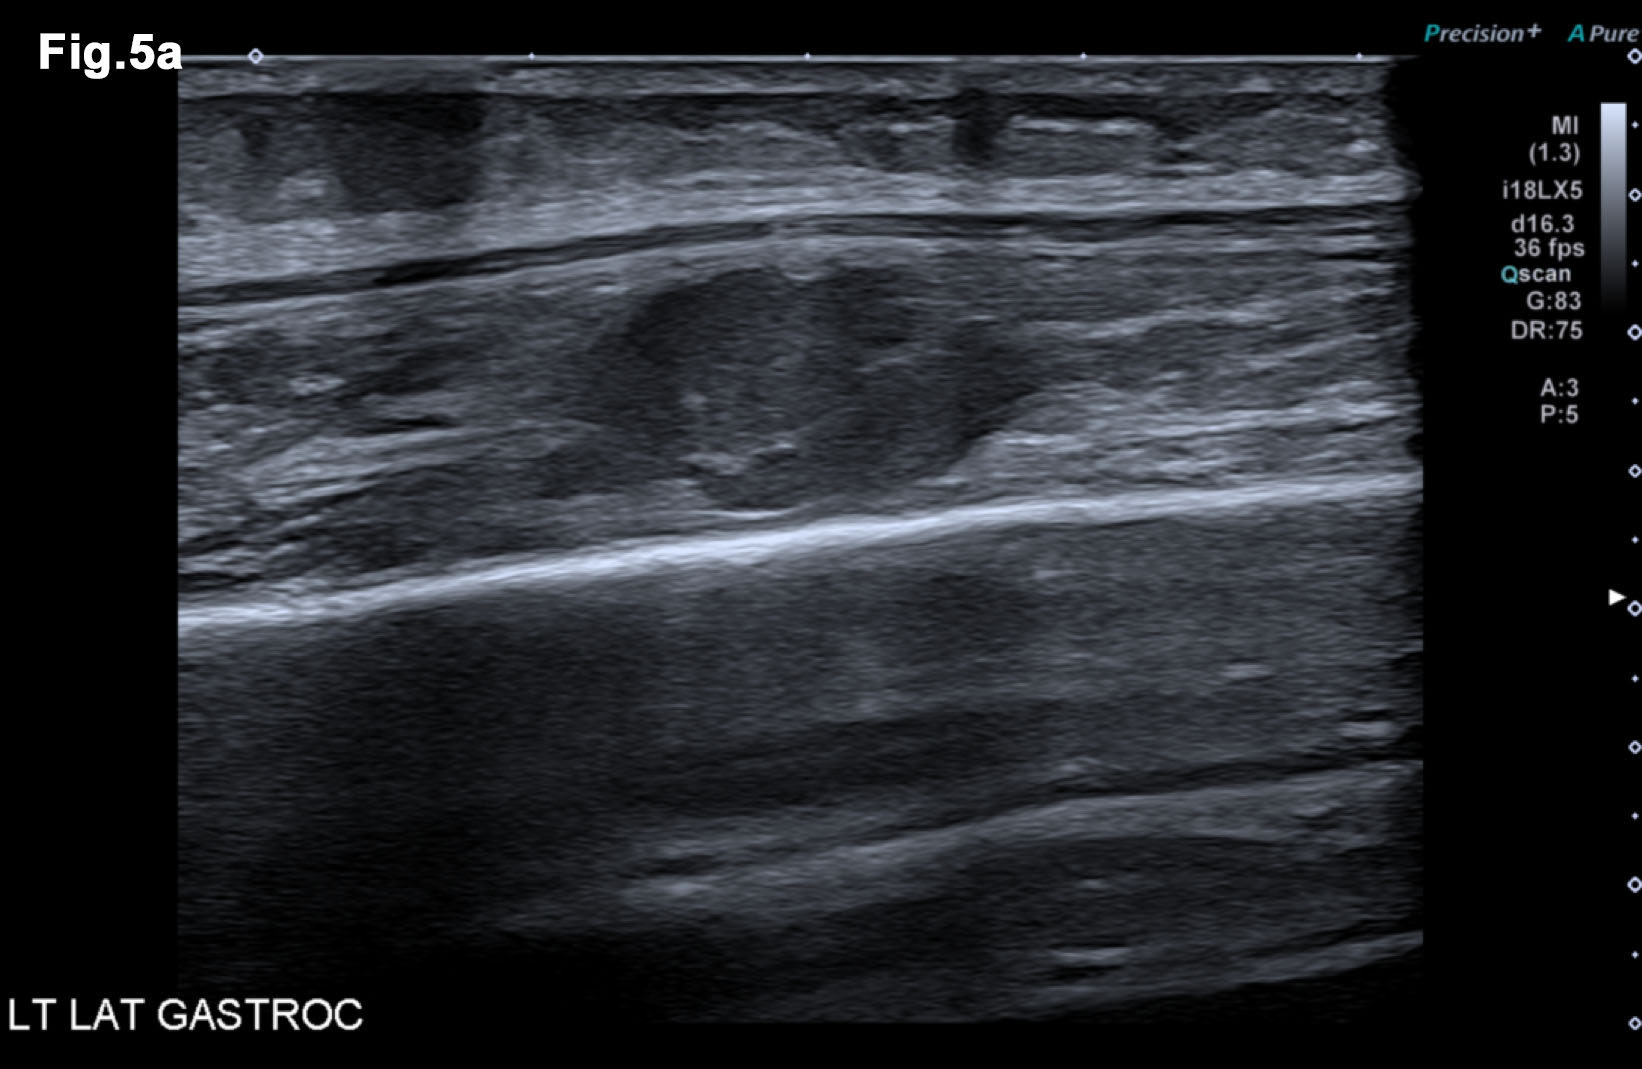

Figure 5 – New presentation of left calf pain with clinical suspicion of a deep venous thrombosis(DVT) – US demonstrated a well-defined hypoechoic mass lesion (a)with moderate vascularity (b) in left gastrocnemius. - Hypoechoic lesion in L gastrocnemius (Fig 5a) - Vascularity demonstrated on Microflow Imaging. (Fig 5b)

- Recent Ultrasound 2018 (Figure 5)

- There was an irregular mass in the left gastrocnemius at the site of tenderness. It was moderately vascular and was subsequently biopsied to reveal a new metastatic deposit similar to the previous lesions and thus disease progression.